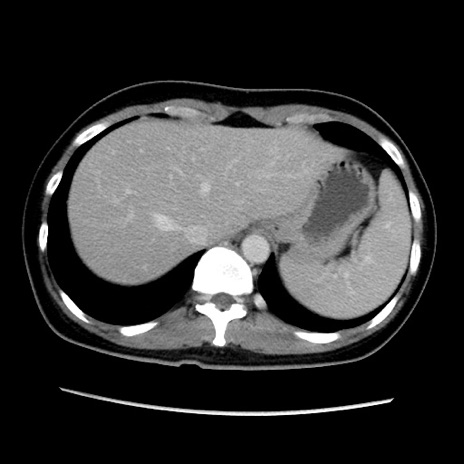

症例39(横断像)

【症例】40歳代女性

【主訴】上下腹部痛

【現病歴】2日目から下腹部痛あり。夜間は痛みで眠れなかった。昨日より上腹部痛と下痢が出現。臥位で痛みは軽快したため、休んでいた。本日になって臥位でも立位でも痛みが強くなってきたため救急要請。

【既往歴】子宮内膜症

【身体所見】部:平坦・軟、左上下腹部に圧痛あり、反跳痛あり。

【データ】WBC 21800、CRP 26.78